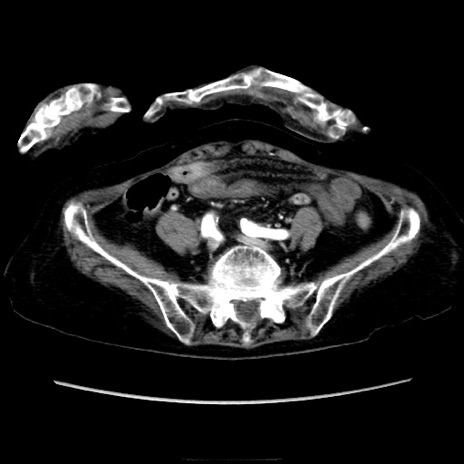

症例40(横断像)

【症例】90歳代女性

【主訴】腹痛・嘔吐

【現病歴】 食欲低下、嘔吐があり昨日他院受診。肺炎と診断され入院となる。入院後より腹部全体に圧痛あり。胃管留置され経過みていたが、症状持続するため、

当院転院となる。

【既往歴】胸椎圧迫骨折、胆石症

【身体所見】腹部:中央に激痛あり、圧痛あり、反跳痛不明

【データ】WBC 17100、CRP 18.82